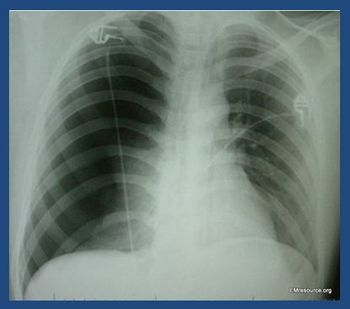

The patient reports the chest pain began 6 days ago during a vacation abroad. She denies any injury. What does the chest x-ray reveal?

Two hours earlier the patient had vomited to dislodge food stuck in his throat. This had been effective in the past but had never produced blood. Chest and epigastric pain worsened when he lay down.